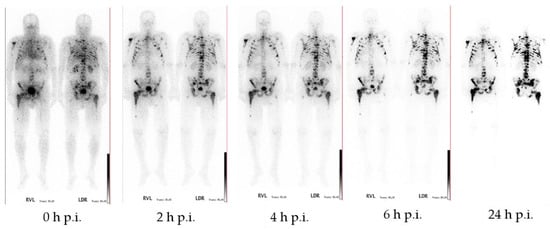

- Fellner, M.; Biesalski, B.; Bausbacher, N.; Kubícek, V.; Hermann, P.; Rösch, F.; Thews, O. 68Ga-BPAMD: PET-imaging of bone metastases with a generator based positron emitter. Nucl. Med. Biol. 2012, 39, 993–999. [Google Scholar] [CrossRef]

- Fellner, M.; Baum, R.P.; Kubíček, V.; Hermann, P.; Lukeš, I.; Prasad, V.; Rösch, F. PET/CT imaging of osteoblastic bone metastases with 68Ga-bisphosphonates: First human study. Eur. J. Nucl. Med. Mol. Imaging 2010, 37, 834. [Google Scholar] [CrossRef]